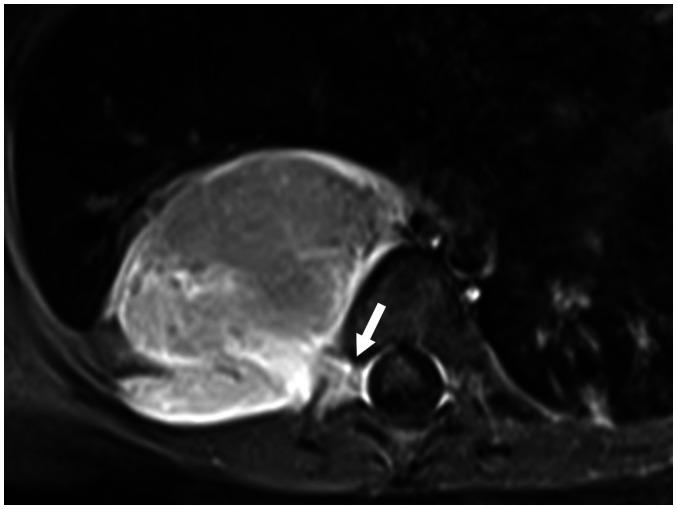

Magnetic resonance imaging (MRI) has become a crucial tool for evaluating mediastinal masses considering that several lesions that appear indeterminate on computed tomography and radiography can be differentiated on MRI. Using a three-compartment model to localize the mass and employing a basic knowledge of MRI, radiologists can easily diagnose mediastinal masses. Here, we review the use of MRI in evaluating mediastinal masses and present the images of various mediastinal masses categorized using the International Thymic Malignancy Interest Group's three-compartment classification system. These masses include thymic hyperplasia, thymic cyst, pericardial cyst, thymoma, mediastinal hemangioma, lymphoma, mature teratoma, bronchogenic cyst, esophageal duplication cyst, mediastinal thyroid carcinoma originating from ectopic thyroid tissue, mediastinal liposarcoma, mediastinal pancreatic pseudocyst, neurogenic tumor, meningocele, and plasmacytoma.

磁共振成像(MRI)已成为评估纵隔肿块的重要工具,因为 CT 和 X 线摄影上表现为不确定的一些病变可以在 MRI 上区分。使用三室模型定位肿块并运用 MRI 的基本知识,放射科医生可以轻松诊断纵隔肿块。在这里,我们回顾了 MRI 在评估纵隔肿块中的应用,并展示了使用国际胸内恶性肿瘤兴趣小组的三室分类系统对各种纵隔肿块进行分类的图像。这些肿块包括胸腺增生、胸腺囊肿、心包囊肿、胸腺瘤、纵隔血管瘤、淋巴瘤、成熟畸胎瘤、支气管囊肿、食管重复囊肿、起源于异位甲状腺组织的纵隔甲状腺癌、纵隔脂肪肉瘤、纵隔胰腺假性囊肿、神经源性肿瘤、脑脊膜膨出和浆细胞瘤。